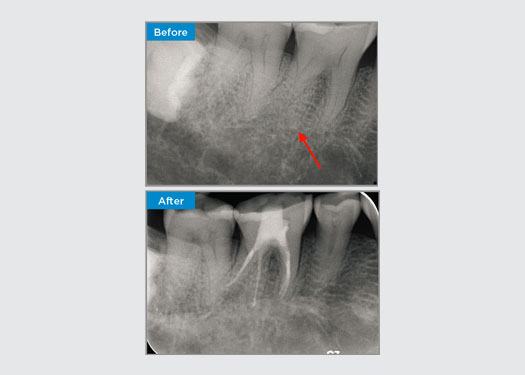

Le patient présentait une parodontite apicale asymptomatique sur la dent 34. Sur la radiographie préopératoire, la dent 34 était notée avec deux racines visibles. Cependant, un scanner CBCT a confirmé une prémolaire à trois racines, les canaux se divisant en trois au milieu de la racine. Une sélection minutieuse des limes est essentielle pour cette dent délicate.

Dans cette situation, la préservation de la structure de la dent/racine est essentielle pour réduire le risque de déviation, de transport, de radiculalgie, de perforation et de fracture de la racine. La sélection des cas, le diagnostic et la planification avant le traitement sont importants. La sélection de limes endodontiques avec flexibilité, efficacité et respect de l’anatomie naturelle de la racine est essentielle.

La patiente présentait une pulpite irréversible sur la dent 46. D’après la radiographie préopératoire, la dent 46 présente une racine distale supplémentaire (morphologie de la dent Radix Entromolaris). Une scintigraphie CBCT a confirmé la présence de la racine DL avec une courbure sévère de la racine. Une sélection minutieuse de la lime est essentielle pour cette racine DB délicate.